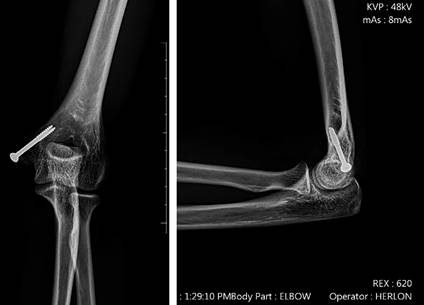

Figura 9: Radiografía en proyección anteroposterior y lateral de una paciente de 15 años con fractura del epicóndilo medial.

Figura 10: Radiografía en proyección anteroposterior y lateral, dos años después de la cirugía de fractura del epicóndilo medial del húmero fijada con la técnica «Inside-out».